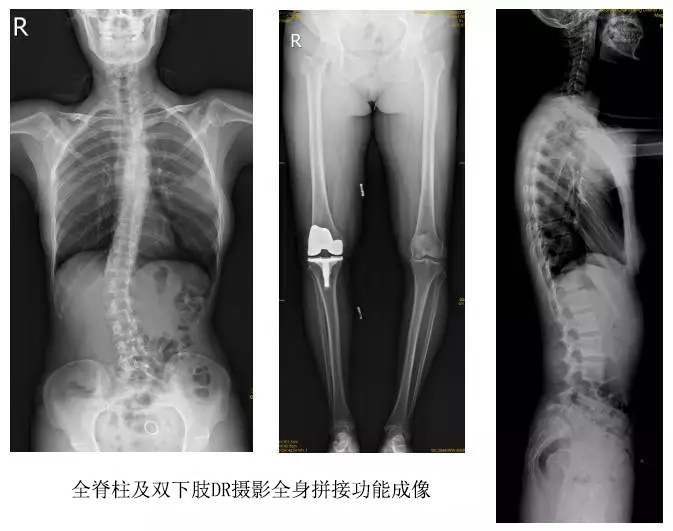

技術(shù)日新月異,隨著DR全身拼接功能的可實(shí)現(xiàn),有效解決了全脊柱及全下肢的完整成像。

以某院所攝X光片為例,對(duì)比傳統(tǒng)攝片與全身拼接功能的區(qū)別:

傳統(tǒng)X光片只能觀察每個(gè)部位的局部情況,無法在統(tǒng)一體上進(jìn)行連續(xù)、全面的觀察,全脊柱及下肢全長片則能直觀的看到整體形變。通過DR全身拼接功能實(shí)現(xiàn)的完整成像,為診治脊柱及下肢畸形提供了完美的臨床影像依據(jù),對(duì)臨床診斷、術(shù)前手術(shù)方案的制定和術(shù)后療效的評(píng)估等臨床應(yīng)用具有十分重要的意義,有效滿足了此類疾病臨床診斷和治療的要求。

通過以上對(duì)比,可以發(fā)現(xiàn),在缺少DR全身拼接功能的條件下,傳統(tǒng)X光攝片無法有效解決骨科常見疾病如脊柱側(cè)彎及下肢畸形的臨床診斷。在國家大力推進(jìn)健康中國、人民不斷增長的醫(yī)療需求的大背景下,醫(yī)療缺陷將不斷被合理技術(shù)替代,因此從對(duì)立面評(píng)測,如今,沒有全身拼接功能的DR就不是合格的DR。